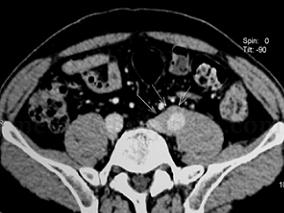

1小时条评论【病例资料】 患者男性,54岁。 主诉:左下腹痛1个月。 现病史:患者2009年2月8日晚无明显诱因出现左下腹绞痛,无放射,不伴腹泻、恶心、呕吐、发热,与体位、进食无明显关系。2009年2月9日于我院急诊就诊,查肾功能Cr 168mu;mol/L,B超提示左肾积水,左侧输尿管...